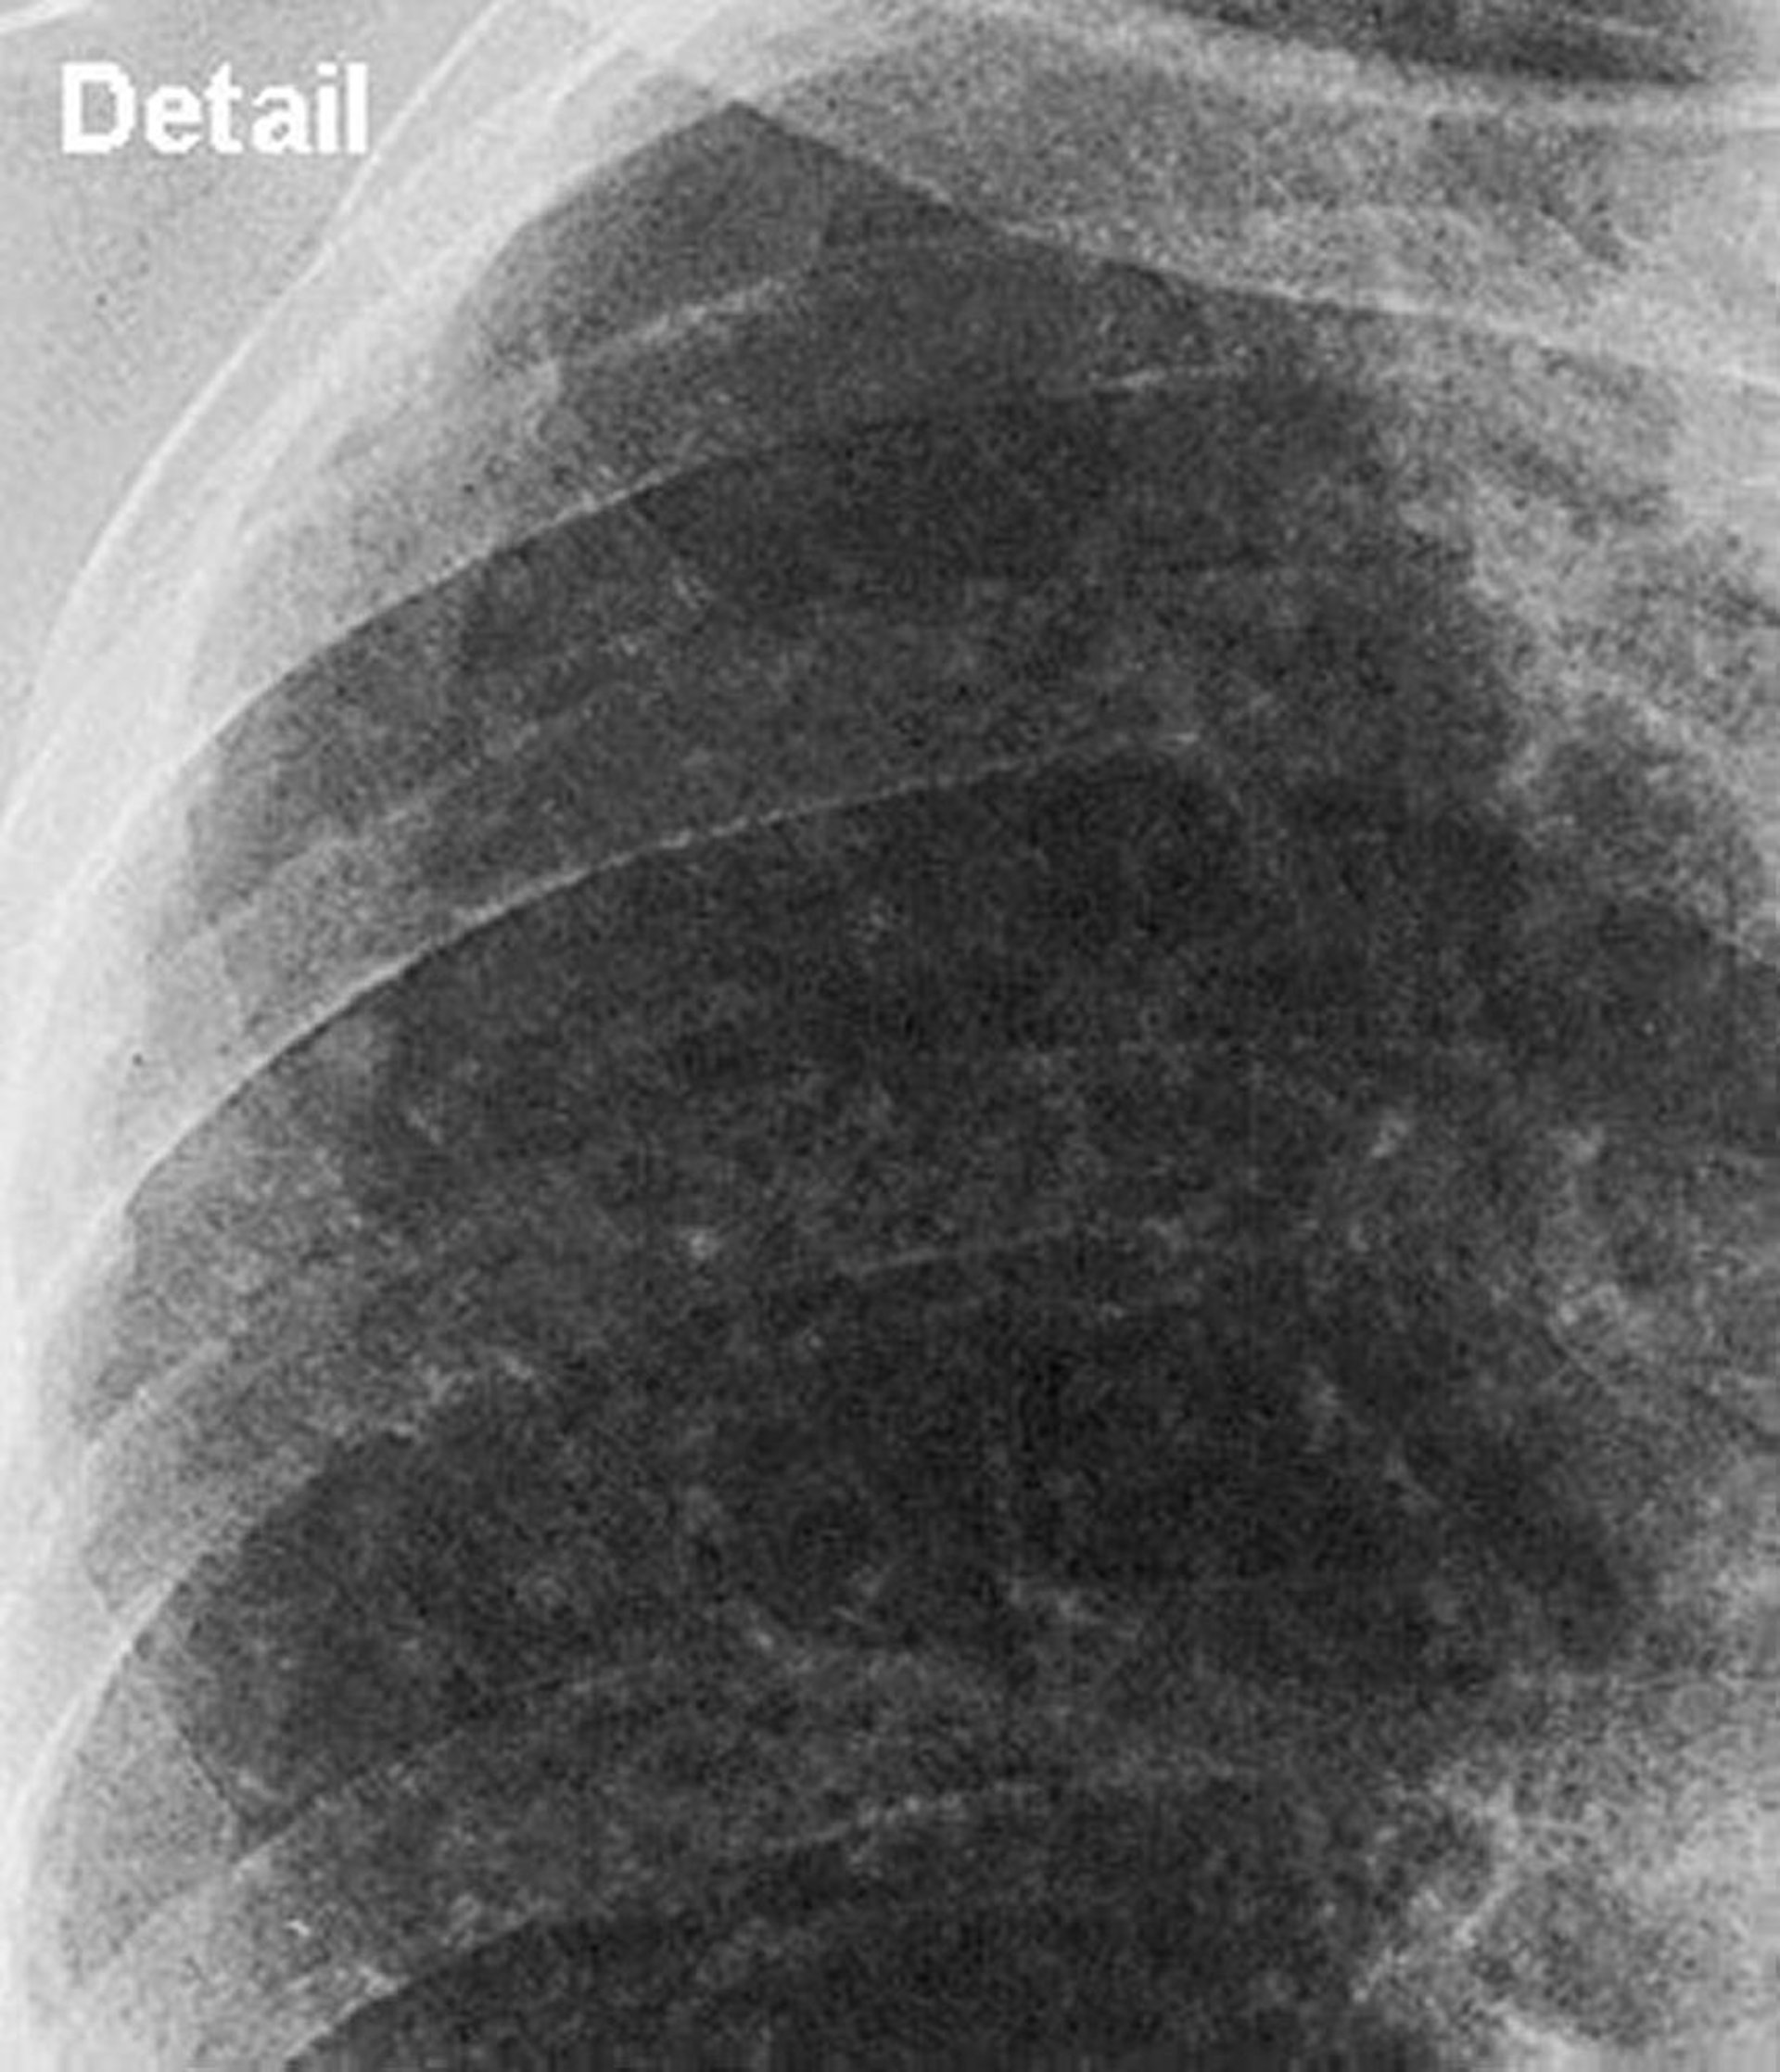

珪肺症—単純性(上肺野)

単純性珪肺症の上肺野の拡大像。

Image courtesy of David W.Cugell, MD.